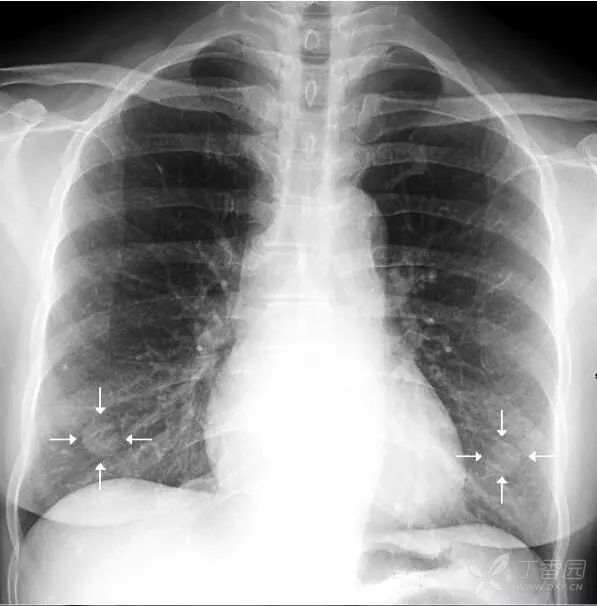

肩胛骨 如果投照时体位标准,上肢内旋充分,则肩胛骨应当位于肺野之外。否则肩胛骨将重叠于上肺野偏外的区域,呈与胸壁平行的条带状高密度影。此时可能会被误认为是肺内病变。仔细观察可见肩胛骨影从肺内向肺外延伸,即可与肺内病变区别。

上图摄片时双上肢未充分内旋,导致双侧肩胛骨大部分重叠于双肺中上肺野中外带,导致相应肺野条带状密度增高。白色箭头标示右侧肩胛骨内侧缘,向肺外延续。左侧肩胛骨情况类似。